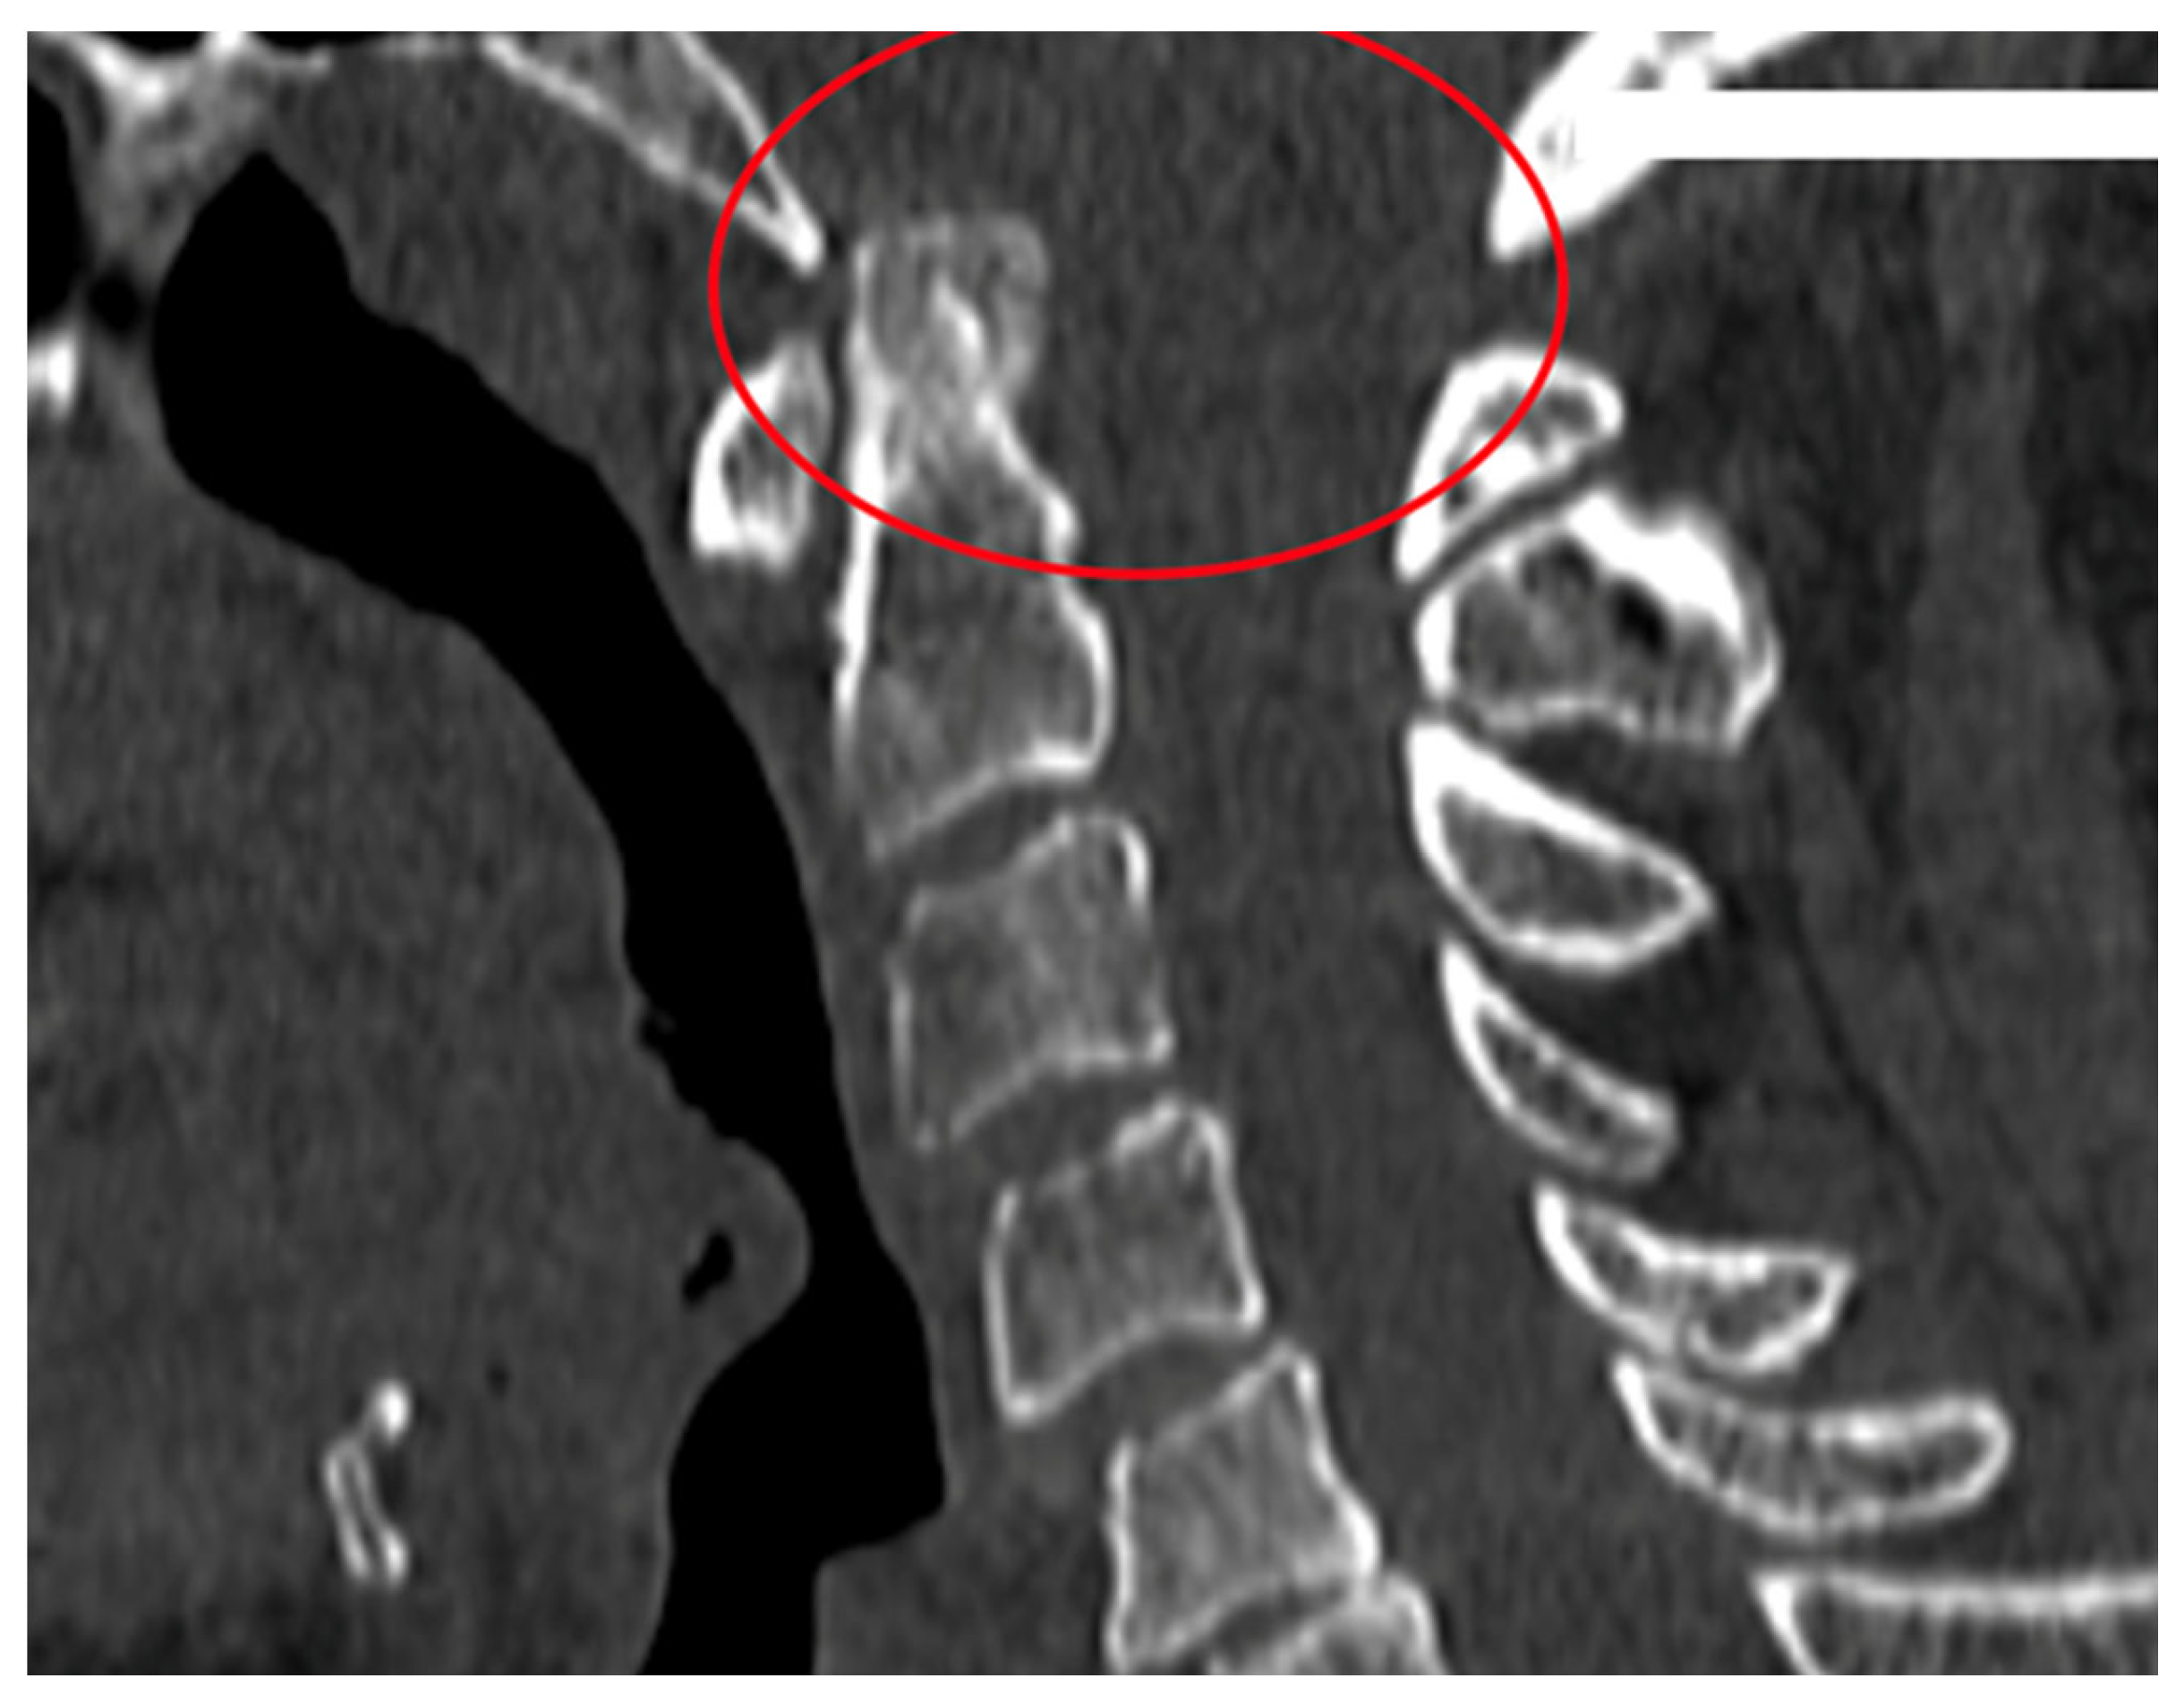

Figure 3.

A 61-year-old patient with RA and CrS instability. Cervical CT.